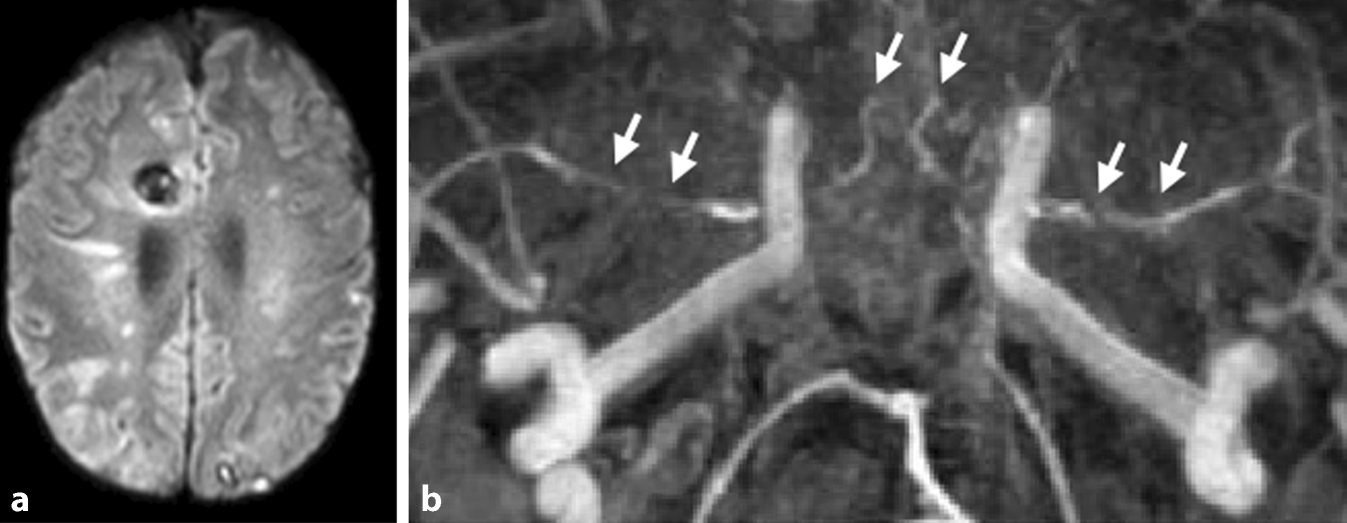

Etwa 20 % der PatientInnen mit bakterieller Meningitis erleiden innerhalb der ersten Wochen nach der Diagnosestellung einen ischämischen Schlaganfall [36]. Neben der bakteriellen Meningitis gehören zu den erregerbedingten Meningitiden auch solche, die durch Viren, Mykobakterien, Pilze oder Protozoen verursacht werden. Infolge der Entzündungsreaktion können bei nahezu allen Formen der Meningitiden sekundär Schlaganfälle auftreten. Die bakterielle Meningitis kann durch das Auftreten typischer klinischer Symptome (Kopfschmerzen, Fieber über 38 °C, Nackensteifigkeit oder Bewusstseinsstörungen) und die Anzahl der Leukozyten im Liquor (über 1000/μl) und/oder den Nachweis bakterieller Mikroorganismen im Liquor diagnostiziert werden [37]. Zerebrovaskuläre Komplikationen, die neben dem ischämischen Schlaganfall auch Hirnvenen- und Sinusthrombosen, Hirnblutungen sowie mykotische Aneurysmen umfassen, tragen zu einem schlechten Outcome der bakteriellen Meningitis bei. Hinsichtlich der zeitlichen Charakteristik kann ein zweigipfeliger Verlauf mit frühen (Tag 3 und 7) und späten (Tag 14) Schlaganfällen beobachtet werden [36]. Der genaue pathophysiologische Mechanismus zur Entstehung von Schlaganfällen im Kontext der bakteriellen Meningitis ist noch nicht vollständig verstanden, jedoch werden der Nachweis von zerebralem Vasospasmus, Vaskulitis, Gerinnungsstörungen, infektiöser Endokarditis und systemischer Entzündungsreaktionen diskutiert [38]. Inwiefern sich die Entstehungsmechanismen früher und später zerebraler Ischämien unterscheiden, ist zum aktuellen Zeitpunkt ungeklärt. Schlaganfälle infolge einer bakteriellen Meningitis treten häufig disseminiert in beiden Hemisphären lokalisiert auf (Abb. 2a). Interessanterweise konnte in einer Fallserie gezeigt werden, dass die Schlaganfälle vor allem in den Versorgungsgebieten von Arterien auftreten, die sich in der Nähe des Infektionsfokus, wie z. B. einer Mastoiditis, befinden [36]. Das Risiko eines ischämischen Schlaganfalls ist unabhängig vom identifizierten Erreger [36]. Eine Vaskulopathie infolge einer bakteriellen Meningitis lässt sich am sensitivsten anhand multipler intraduraler Gefäßverengungen in der Angiographie nachweisen (Abb. 2b).

Abb. 2

Magnetresonanztomographische Aufnahmen eines Patienten mit bakterieller Meningitis infolge einer Mastoiditis rechts. a Die DWI(„diffusion weighted imaging“)-Wichtung zeigt multiple zerebrale Ischämien im vorderen und hinteren Stromgebiet sowie putrides Sediment, hauptsächlich innerhalb der rechten Hemisphäre mit räumlichem Bezug zur Mastoiditis auf dieser Seite. b In der TOF(„time-of-flight“)-Angiographie sind multiple Verengungen der intraduralen Abschnitte der hirnversorgenden Gefäße als Ausdruck einer Vaskulopathie nachweisbar (Pfeile)